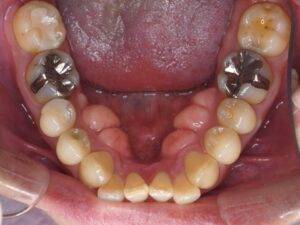

初診時口腔内。前歯部の反対咬合(クロスバイト)およびクラウディング(叢生、乱杭歯)の改善を希望し来院。小臼歯部には鋏状咬合(シザーズバイト)も認め、咬合状態は良くない。下顎歯列弓はやや横幅が狭窄したV字型を呈し、顎骨と歯の大きさのディスクレパンシーは大きくない。前歯部の歯軸および突出感もあまりないため、下顎歯列の側方拡大による非抜歯矯正が可能と判断される。

矯正治療後口腔内。非抜歯側方拡大によるワイヤー矯正を行った(ディスキングなし)。前歯部の反対咬合(クロスバイト)およびクラウディング(叢生、乱杭歯)が改善しているのが分かる。上下の歯列弓は、左右対称の美しいU字型のアーチフォームに修正され、小臼歯部の鋏状咬合(シザーズバイト)も改善し、咬合状態が正常化した。非抜歯ケースであるため、治療期間も最小限。